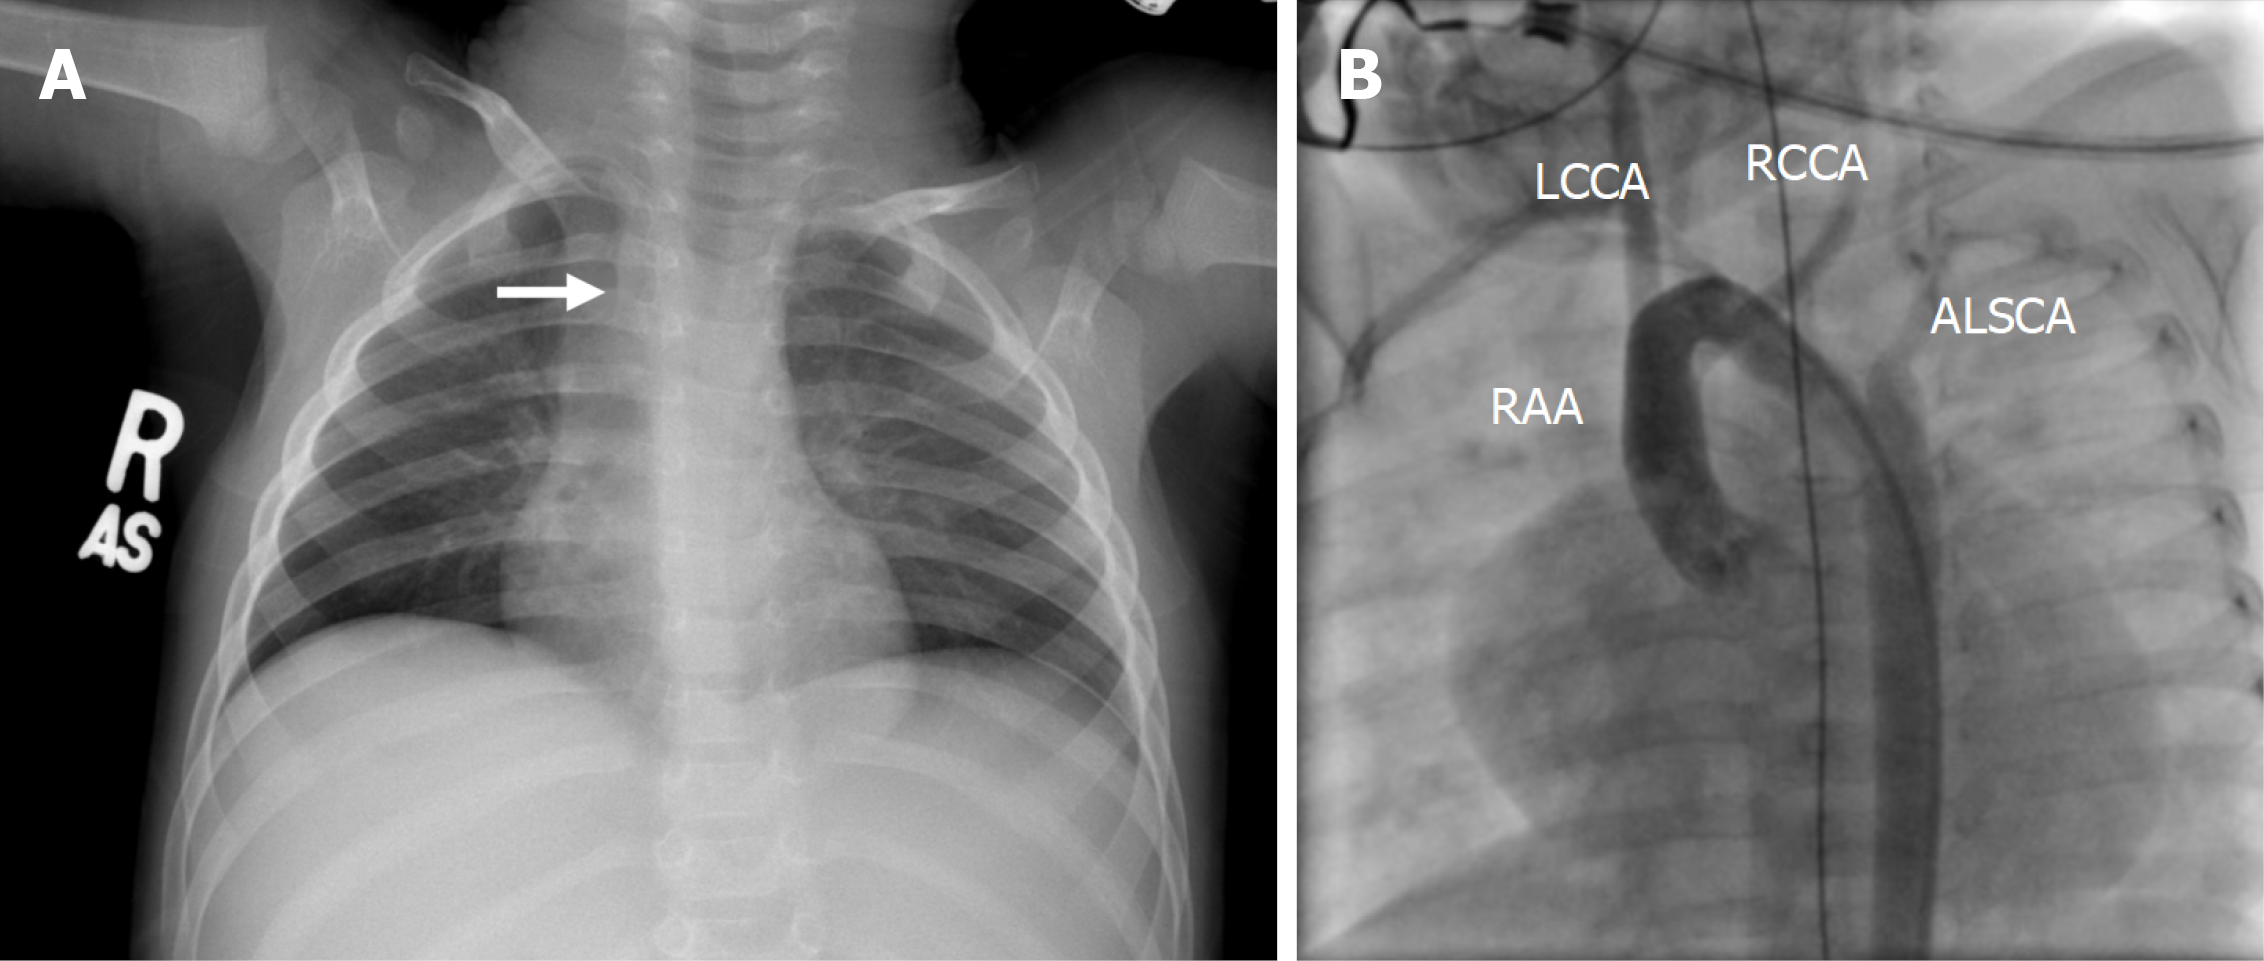

Figure 1 illustrates the echocardiographic findings of a 38-month-old patient with DAA, and Figure 2A shows the corresponding chest radiograph. Notably, this patient had previously been diagnosed with asthma and experienced recurrent respiratory infections requiring multiple antibiotic courses and repeated hospitalizations prior to definitive diagnosis.

All patients underwent preoperative TTE and CTA for anatomical delineation (Figures 3 and 4). One patient additionally underwent diagnostic cardiac catheterization (Figure 2B).